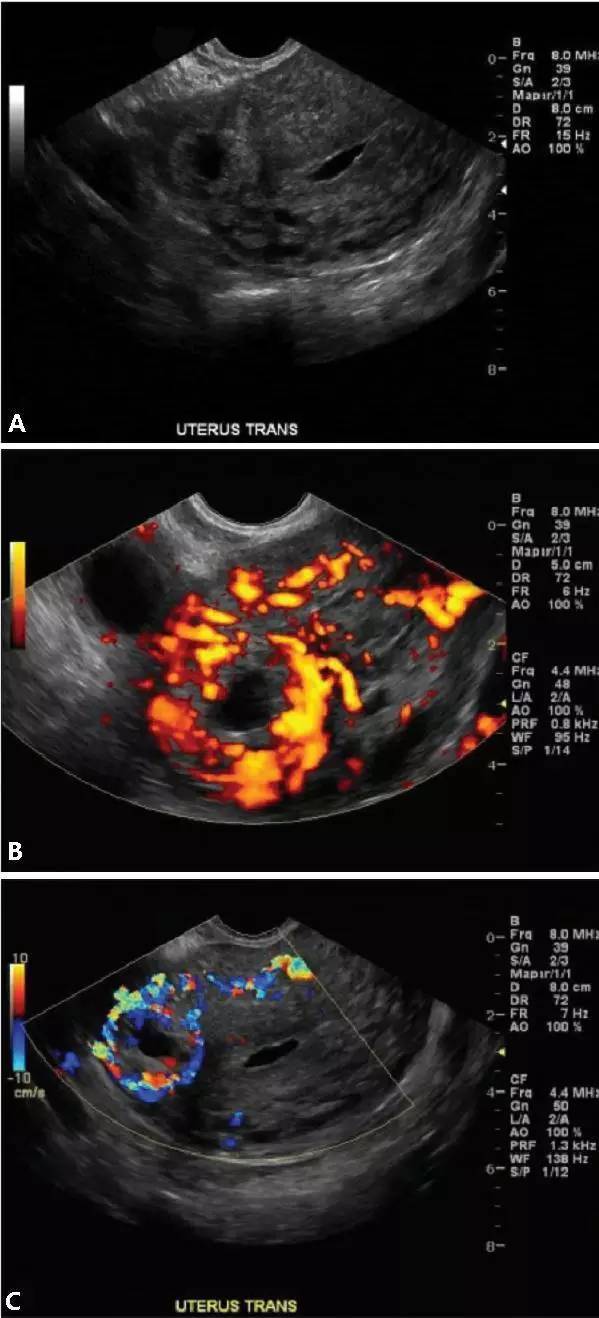

圖 6 輸卵管間質部妊娠聲像圖;橫切面圖像(A)顯示子宮右側壁內可見一高回聲區,其周圍僅有較薄的肌層環繞;橫切面能量多普勒和彩色多普勒圖像(B 和 C)顯示血供增多,提示存在間質部妊娠